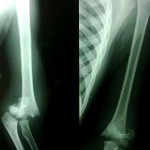

A 12 year old obese boy, presented with pain in the hip for the last 15 days. He is unable to walk now. There has been no similar episode in the past. What is the preferred treatment now

This is a severe unstable slip

Need to work up for endocrinological and metabolic causes

if it is redused even with a gentle closed reduction and fixed there are high chances of AVN 30 to 50 % This is primarily because of kinking of MCF vessel by posterior callus

If oinned in situ AVN can be avoided but it leads to femoro acetabular impingement and a deformity which will not remodel

My choice is to do safe surgical dislocation of hip using Ganz approach do modified dunn procedure to correct femoral hrad alignment by shortening and excision of callus and fix with a cancellous screw